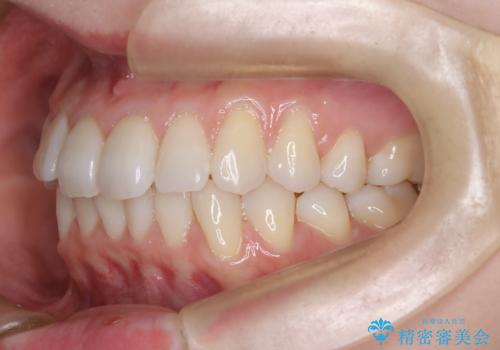

インビザラインモデレートによる前歯の叢生改善|IPR最小限で自然な歯並びへ

- 患者様は、**前歯の叢生(がたつき)**を気にされて来院されました。

できるだけ歯を削らずに、自然な歯並びを手に入れたいというご希望がありました。

診査の結果、中等度の叢生であったため、インビザラインモデレートでの対応が可能と判断しました。

歯へのダメージを抑えるため、IPR(歯間削合)は必要最小限にとどめる方針としました。

前歯の叢生は解消され、自然で調和の取れた歯並びが得られました。

「歯をほとんど削らずにきれいになった」と、患者様にもご満足いただけました。